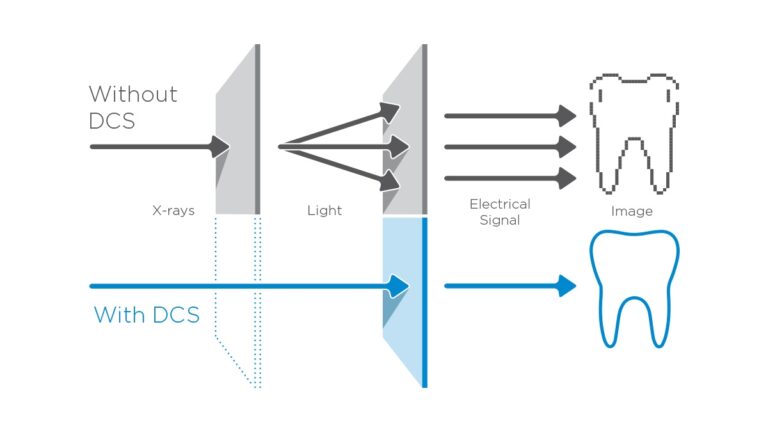

新たなパノラマテクノロジー「DCSセンサー」

Direct Conversion Sensor(DCS)を用いた新たなパノラマX線撮影。X線が電気信号に直接変換されるため、従来のシステムのような光変換に伴う信号ロスが生じません。精細度の高い画像が得られます。